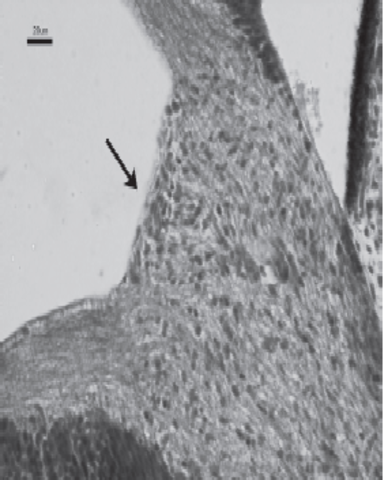

Los axones de las células ganglionares de la retina neurosensorial crecen hacia el pedículo o tallo óptico. De esta manera, la cavidad del tallo se va obliterando. La aparición de los axones en la futura papila se observa en embriones de 16 mm de longitud. Las células del pedículo óptico rodean cranealmente a estas fibras y a la arteria hialoidea

Durante el segundo mes del desarrollo comienza el cierre de la

hendidura embrionaria, debido al crecimiento de los bordes del pedículo óptico. Inicialmente se fusiona la porción intermedia y se extiende en sentido proximal y distal, hasta que a los 20 mm de longitud queda totalmente obliterada. Se observa el quiasma óptico. En la región de la futura papila aparece una acumulación de glioblastos,separando las fibras del nervio óptico del vítreo secundario

Limitante de glioblastos en trayecto intravitreo de la arteria hialoidea

Al final del período embrionario, el nervio óptico presenta un trayecto que va desde la parte posterior del globo ocular hasta el quiasma. Los glioblastos se acumulan en la papila, separan las fibras nerviosas en la región coroidea, separándolo del mesénquima vecino. Las funciones que tienen en el adulto son de protección y soporte en su giro, de resistencia a las presiones con los movimientos y de organización de los haces a su paso por la lámina cribosa.